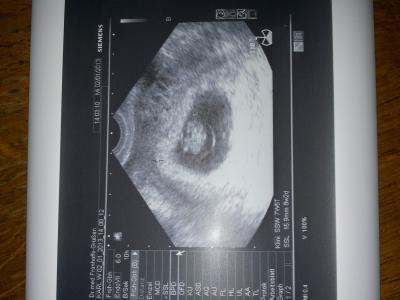

Das war super kleines kaffeebönchen gesund und munter,Herzchen puckert alles super *freuuu am 30.1 nächster termin

Wow glückwunsch!! Soo groß ist es schon!! Wie weit bist du genau? Ich 7+2 ssw! Und wie groß ist es? Lg

Bin heute 7+5.....